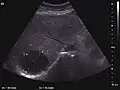

Regenerative nodule (CEUS). One can see the hypovascular pattern of the solid nodule, with a size <10 mm.

These lesions are well defined, with isoechoic or hypoechoic appearance and sizes less than 1 cm. They are high in numbers and have a more or less uniform distribution, involving all liver segments. They can crowd resulting in large pseudo tumors. At Doppler examination, these nodules have no circulatory signal. CEUS exploration is indicated when a nodule is different against the general pattern of restructured liver either by different echogenity or by a different size than the majority of nodules. During the arterial phase, the signal is weak or absent. During the portal venous and late phase, the appearance is persistently isoechoic.

Generally, RN is not distinct from the surrounding parenchyma. CEUS examination is useful to exclude an active lesion at the moment of exploration but does not have absolute prognostic value; therefore the patient should be periodically examined at short intervals. Correlation with clinical status and AFP measurements is required.

Dysplastic nodule (2D, CFM, CEUS). The nodule is well-defined with a size between 10– 20 mm, lacks vessels in CFM and CEUS exploration.

These lesions have various patterns (hypo or hyperechoic) with at least 1 cm diameter. They are hepatocytes with dysplastic changes, but without clear histological criteria for malignancy. They are divided into low-grade dysplastic nodules, where cellular atypia are mild and high-grade dysplastic nodules with moderate or severe cellular atypia, but without any established signs of malignancy. Occasionally, well-differentiated HCC foci can be identified in high-grade dysplastic nodules (appearance called "nodule in nodule") . Most authors accept the carcinogenesis process as a progressive transformation of DN from low-grade to high-grade and into HCC. The nodule's vasculature changes progressively, correlated with the degree of malignancy, and it is characterized by decrease until absence of portal venous input and by increase of arterial intratumoral input. Neoformation vessels occur with increasing degree of dysplasia. Arterial neovascularization is enhanced in a chaotic and explosive way, while normal, arterial and portal vasculature continues to decline. High-grade dysplastic nodules are hypovascularized both arterial and portal phases, while early HCC nodules may have similar arterial pattern with the surrounding parenchyma or exacerbated, and portal hypovascularization. In moderate or poorly differentiated HCC (classic HCC) tumor nutrition is performed only by neoformation vessels (abundant), the normal arterial and portal vasculature completely disappearing. This behavior of intratumoral vascularization is typical for HCC and is the key to imaging diagnosis.

B-mode ultrasonography is unable to distinguish between regenerative nodules and borderline lesions such as dysplastic nodules and even early HCC. Doppler examination also has a low sensitivity in differentiating dysplastic nodules from early HCC. Doppler signal may be absent in both regenerative and dysplastic nodules. Some authors indicate the presence of venous type Doppler flow which reflects the portal venous nutrition of the nodule as a characteristic feature of dysplastic nodules and early HCC (Minami & Kudo, 2010). Other authors noticed the presence of an arterial flow with small frequency variations and a normal resistivity index. On CEUS examination both RN and DN may have quite a variable enhancement pattern. Generally, both nodules enhances identically with the surrounding liver parenchyma after UCAs injection. Dysplastic nodules are hypovascular in the arterial phase. In case of highgrade dysplastic nodule sometimes a hypervascularization can be detected, but without associating "wash out" during portal and late CEUS phases. In these cases, biopsy may clarify the diagnosis.